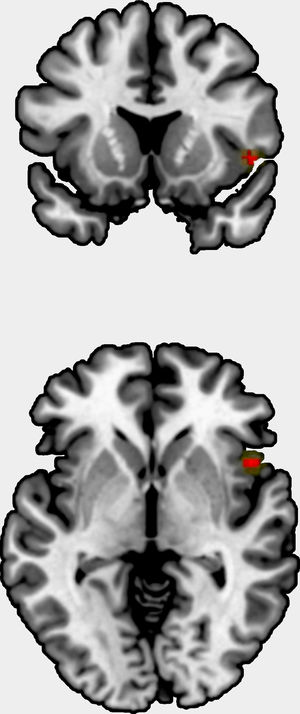

We could include 11 studies to the meta-analysis, comprising one original statistical map,65 eight studies reporting several peaks, and three studies with no findings. The studies comprised 710 patients, and the original statistical map 264 patients. The meta-analysis showed a positive correlation between grey matter volume/cortical thickness and insight in right insula, Brodmann area 48 (peak at MNI=[48,14, −2], Z=3.8, uncorrected p=0.00006, Fig. 2). This result showed neither substantial heterogeneity (I2=2.4%) nor hints of publication bias (Egger's test p=0.79), and it was not statistically significant after FWER correction for multiple voxel testing.

The meta-analysis showed an uncorrected positive correlation between grey matter volume/cortical thickness and insight in the right insula. As a major component of the “limbic integration cortex,” the insula is widely interconnected with cortical and limbic areas.66

The insula is a key component of a general salience network,67 prompting us to believe that insular dysfunction and alterations between network interactions might be characteristic of schizophrenia. The decrease in grey matter volume has been associated with neurological soft signs in ultra-high risk subjects.68 As such, because the insula plays a role in self awareness,69 it could also be linked to a patient's ability to recognize that his or her symptoms stem from the illness.